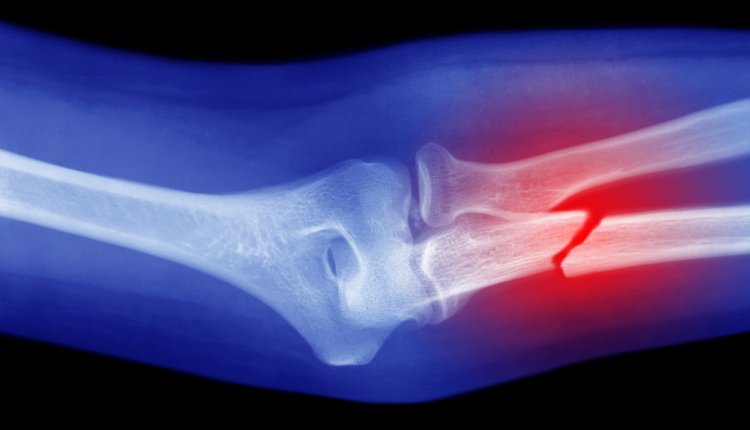

Chinese onderzoekers hebben een - volgens hen - revolutionaire 'superlijm' voor botten ontwikkeld. Met de bottenlijm kunnen breuken, die normaal gesproken maanden nodig hebben om te genezen, binnen enkele minuten worden hersteld, meldt het AD.

Volgens Lin Xianfeng, orthopedisch chirurg en hoofd van het onderzoeksteam, wordt de lijm in de botten aangebracht door middel van een enkele injectie, zo meldt The Global Times. De lijm met de naam 'Bone-02' lijmt dan 'de gebroken botfragmenten in slechts drie minuten aan elkaar', aldus de chirurg.

Volgens het onderzoeksteam zijn metalen platen om botten aan elkaar vast te zetten in de toekomst niet meer nodig. De lijm zou een maximale hechtkracht hebben van 180 kilo. Daarnaast kan Bone-02 volgens de onderzoekers op natuurlijke wijze door het lichaam worden opgenomen tijdens het genezingsproces van het bot. Een operatie om lijmresten te verwijderen is daardoor niet nodig.